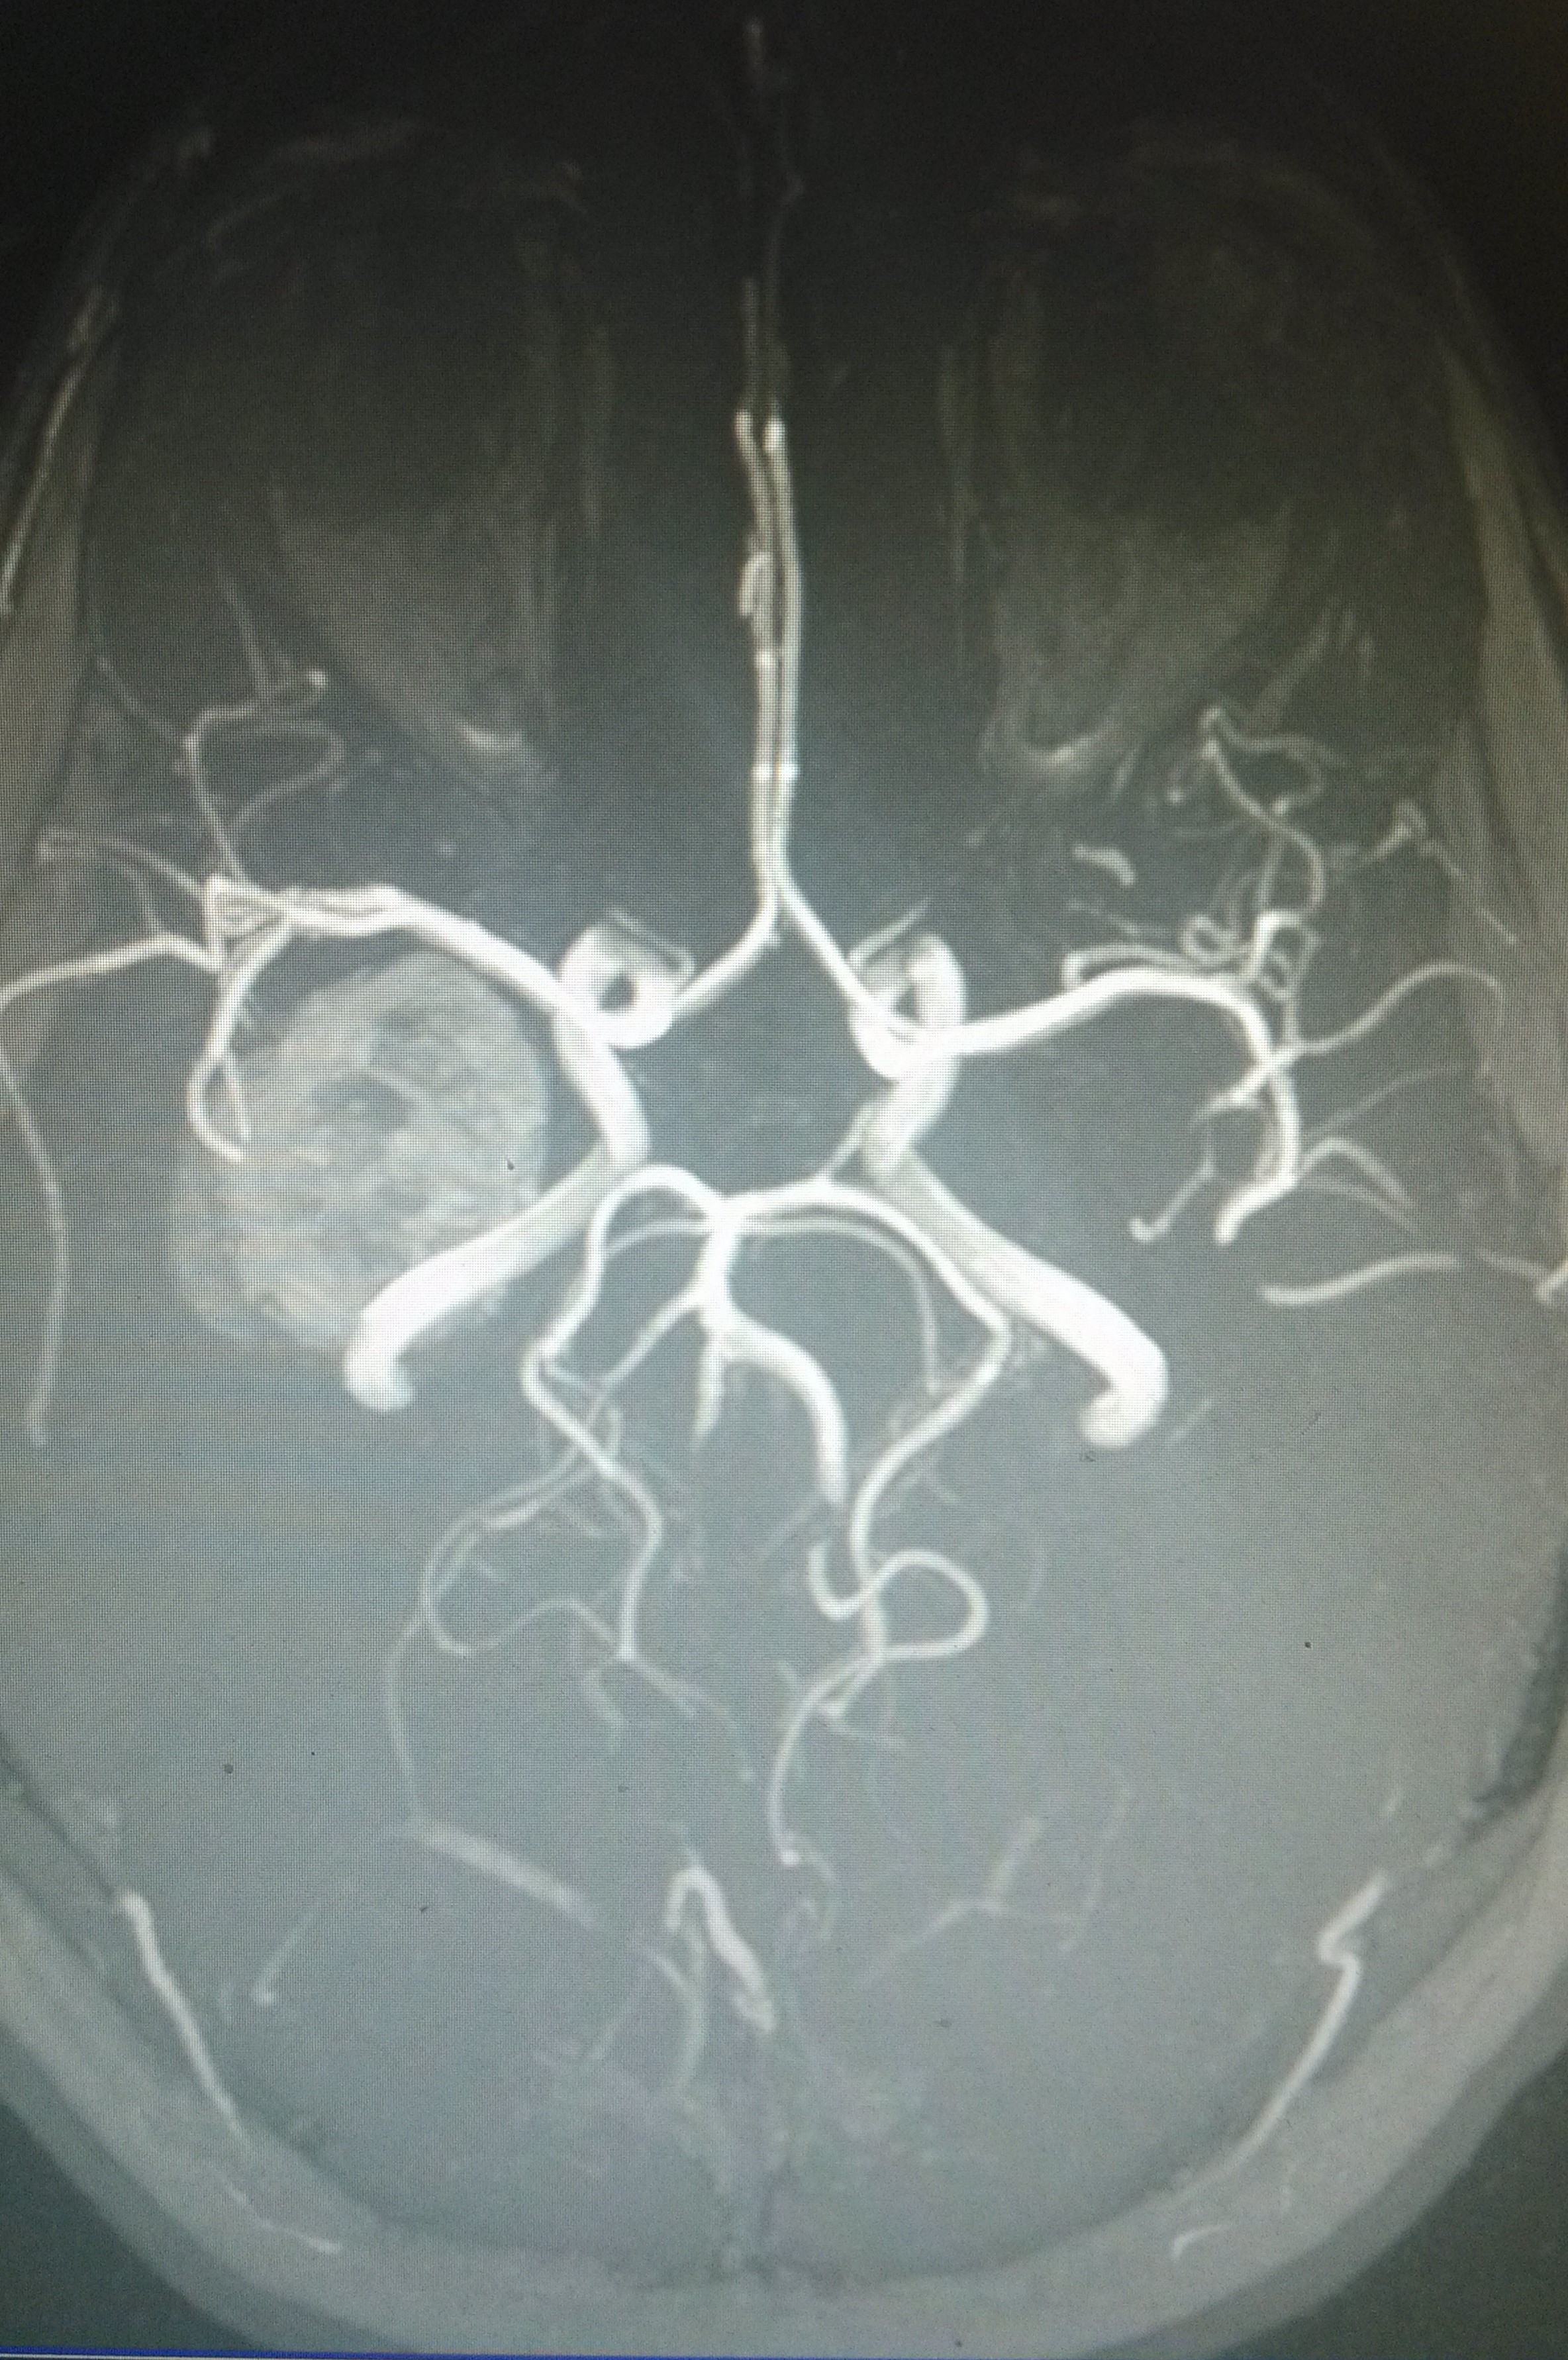

Bis jetzt habe ich immer eine CD vom MRT/CT bekommen.knoxxi schrieb:Was wäre denn die sinnvollere Methode des Austauschs gewesen, offline Medien ausgenommen?

Das beste war, meine Frau ist mit ihrer CD zum Arzt und er konnte es sich nicht angucken weil der PC kein Laufwerk dafür hat o_O.

Btw: kann ruhig jeder sehen :d

Anhänge